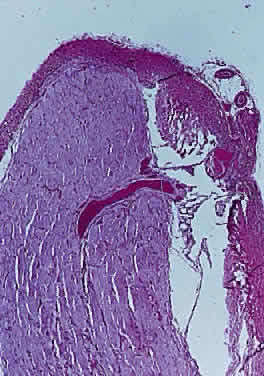

Vascular anomalies stem from a failure of the hyaloid vessel to regress completely or partially. Such anomalies include a Bergmeister's papilla (Fig. 17), persistent hyperplastic primary vitreous (Fig. 18), anomalous distribution of central retinal vessels, epipapillary vascular loops, abnormal chorioretinal anastomosis, and epipapillary membranes.

Fig. 17. Bergmeister's papilla projects from optic disc into vitreous cavity (longitudinal section hematoxylin and eosin staining)